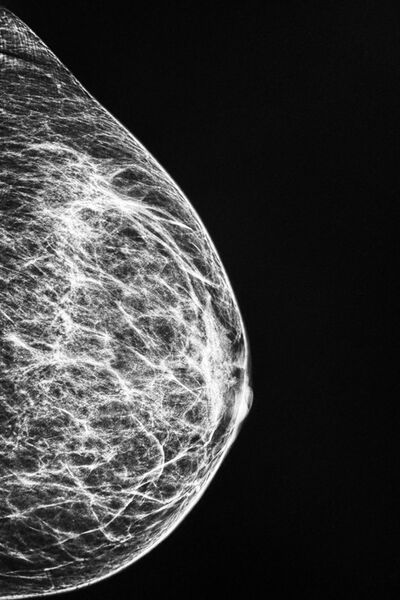

Brustultraschall / Mammasonographie

Der Brust-Ultraschall (Mammasonographie) dient der Untersuchung der Brust. Er wird zur Diagnostik von Gewebsveränderungen der Brustdrüsen angewandt.

Das Verfahren

Der Brust-Ultraschall (Mammasonographie) wird mit unhörbaren Ultraschallwellen durchgeführt, die sich vom normalen Schall durch eine andere Schwingungsfrequenz unterscheiden.

Bei der Untersuchung wird ein durchsichtiges Gel auf die Brust aufgetragen. Der Schallkopf wird mit sanftem Druck über die Brust bewegt. Bilder des Brustgewebes werden auf einen Bildschirm übertragen - das Untersuchungsergebnis liegt somit sofort vor.